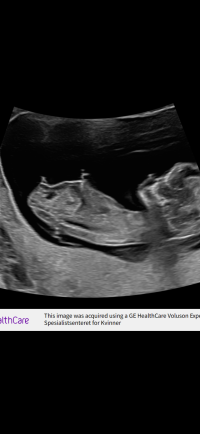

Gløymde å skrive at det var i veke 11+6

Det er for tidlig for nubtheory, frem til 12+3 ser alle like ut. Dvs alle ser ut som jenterGløymde å skrive at det var i veke 11+6![]()

Jeg tror jente, ligner veldig på nuben til jenta vårNoen som vil prøve seg på gjetting hvis nub vises? Jeg har hatt sterk magefølelse to tidligere graviditeter. Denne gangen er jeg mer usikker

Har du noe bilde av det? Hvis du vil deleJeg tror jente, ligner veldig på nuben til jenta vår